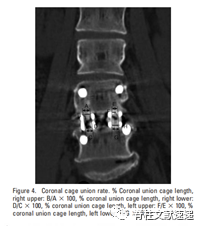

图注:冠状面Cage融合率(%)。右侧Cage内部骨与上侧椎体终板结合处的融合率:B/AX100%;右侧Cage内部骨与下侧椎体终板结合处的融合率:D/CX100%;左侧Cage内部骨与上侧椎体终板结合处的融合率:F/EX100%;左侧Cage内部骨与下侧椎体终板结合处的融合率:H/GX100%。

术后对其随访一年。一年后CT结果示:术后1年椎间高度平均值明显高于术前水平,椎间融合率为96.2%。Cage内部骨与上下终板结合处的融合率在冠状面为46.7%和52.2%,矢状面为46.4%和49.9%(融合率测量方法见上图)。Cage下沉高度在冠状面为1.26mm和0.72mm,矢状面为1.04mm和0.53mm。由此可以看出Cage内部骨的融合率为50%左右。因此作者建议将更多的骨组织移植到椎间隙中,而非Cage内。